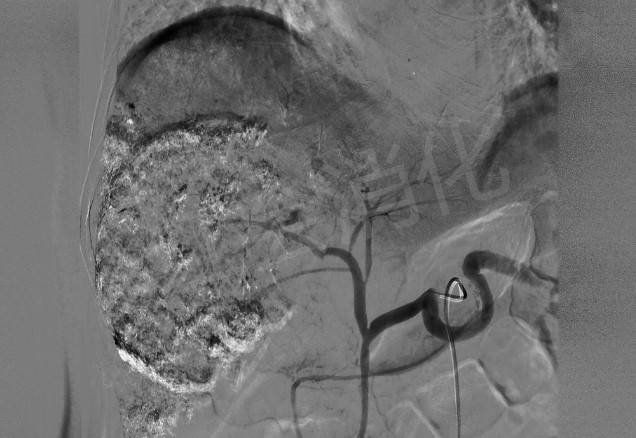

腹主动脉造影 , 明确肝动脉位置

文章图片

栓塞前肝动脉造影 , 可见明显的动脉丛 , 成“球形”包绕